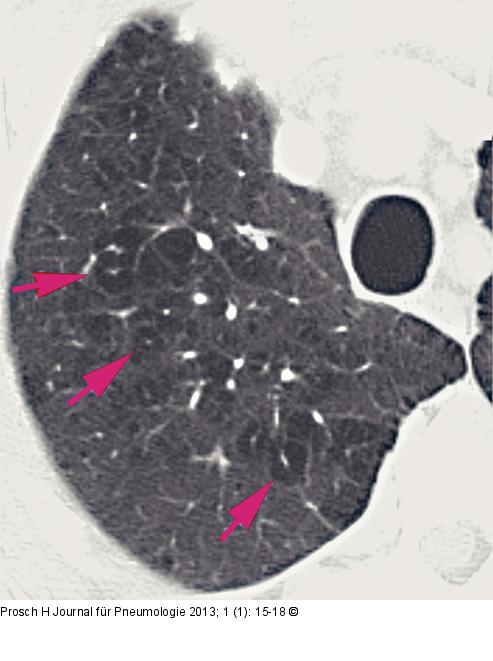

Abbildung 1: Computertomographie-COPD Zentrilobuläres Emphysem bei einem 53 Jahre alten Patienten. Das Lungenemphysem ist durch fokale Areale mit verminderter Lungendichte gekennzeichnet (Pfeile). |

Zentrilobuläres Emphysem bei einem 53 Jahre alten Patienten. Das Lungenemphysem ist durch fokale Areale mit verminderter Lungendichte gekennzeichnet (Pfeile). |